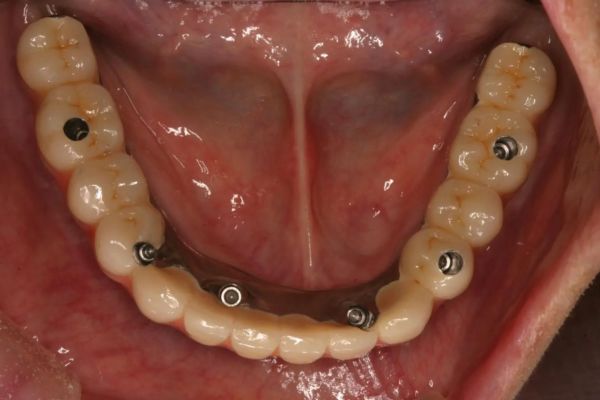

インプラント治療の症例紹介③

Before

After

主訴

むし歯の治療

治療内容

保存不可能な歯の抜歯

下顎にインプラント埋入し咬合再構成

治療費

2,688,400円(税込)

治療期間

14か月

治療回数

21回

想定されたリスク

※上部構造の形態が複雑になるため清掃が難しくなる。インプラント周囲炎の恐れがありました。

多数歯う蝕および多数歯欠損による咬合崩壊、保存不可能な歯の抜歯により上下無歯顎に。下顎に6本インプラント埋入する事で咬合再構成を行った。